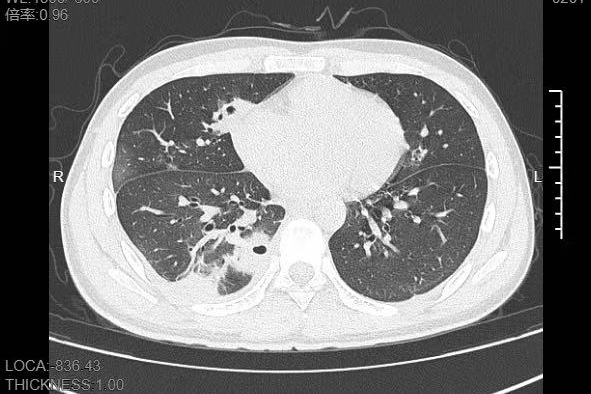

更难受的是右下胸部传来的疼痛,像有根针在扎,深呼吸、咳嗽时更是疼得直冒冷汗。熬到第三天,小林已经烧到39℃,赶紧来到宁波大学附属第一医院就诊。接诊的呼吸与危重症医学科丁群力主任医师一看他的症状,立刻安排了CT检查,结果显示:小林的肺里有十几个空洞,部分肺组织已经坏死,这是典型的血源性肺脓肿。